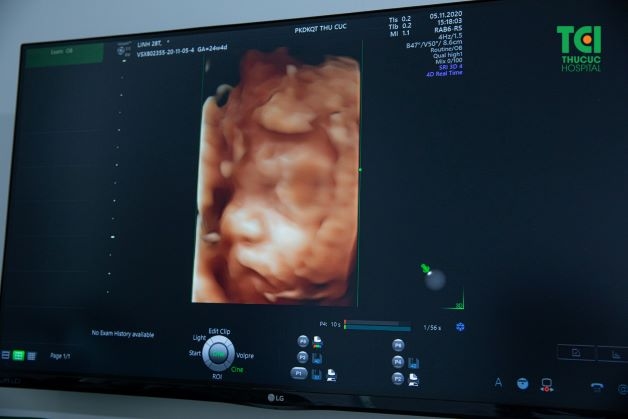

Siêu âm công nghệ 5D là hình thức siêu âm kết hợp của siêu âm 4D và phương pháp siêu âm màu Doppler. Công nghệ siêu âm này có thể giúp quan sát một cách rõ nét và chân thực hình thái, cử động của thai nhi trong bụng mẹ. Đồng thời giúp bác sĩ chẩn đoán, phát hiện sớm các dị tật ngay từ những tháng đầu tiên của thai kỳ.

Siêu âm 5D có thể giúp quan sát một cách rõ nét và chân thực hình thái, cử động của thai nhi trong bụng mẹ